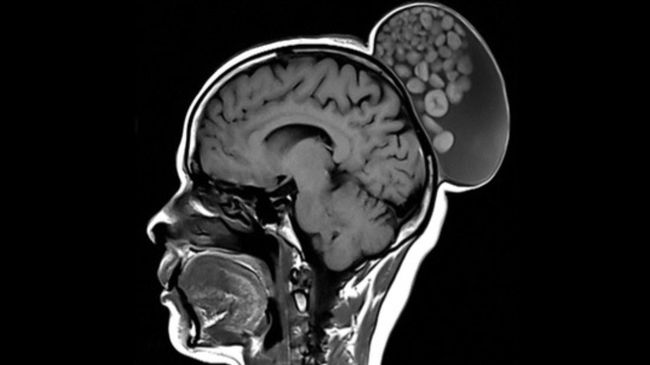

Foto: Benjolan kepala pada wanita India yang ternyata merupakan kista (Radiology Journal)

Dokter yang memeriksakan kondisi wanita tersebut menuturkan, bahwa benjolan tumor tersebut sebenarnya adalah kista. Ukuran panjangnya sekitar 6 inci (15,24 cm), lebar hampir 4 inci (10,16 cm), dan tingginya hampir 5 inci (12,7 cm).

Setelah pemeriksaan lebih lanjut, dokter menemukan banyak 'bola' keratin dalam benjolan tersebut. Benjolan itu tersembunyi di balik kulit kepala dan rambutnya. Bila dilihat sekilas, benjolan tersebut nampak seperti sanggul rambut. Berdasarkan laporan yang dipublikasikan dari Radiology Journal, pasien itu akhirnya menjalani operasi.

"Teratoma kistik dewasa umumnya ditemukan di jaringan gonad dan di daerah kepala dan leher. Di kepala, mereka memiliki kecenderungan untuk muncul di rongga mata dan kulit kepala," tulis tim dokter dalam laporan tersebut.

"'Kelereng' yang ada di dalamnya adalah agregat bulat dari keratin, lemak, bahan sebasea, fibrin, dan rambut yang mengambang di dalam matriks cairan kista. Meskipun jarang terjadi, tanda 'kantong kelereng' dianggap patognomonik teratoma kistik dewasa di kepala dan leher," sambungnya.